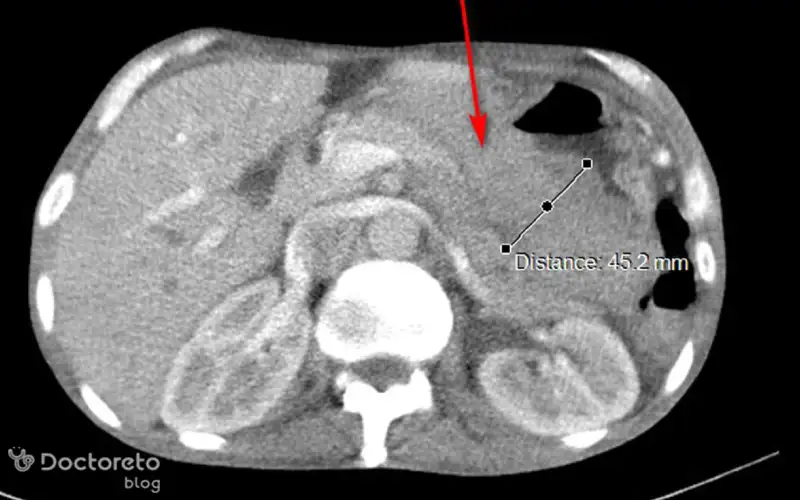

عکس سی تی اسکن سرطان معده بدخیم

در ادامه تصویر سیتیاسکن مربوط به سرطان معده بدخیم را مشاهده میکنید. سیتیاسکن به پزشک اجازه میدهد تا محل، اندازه و گسترش تومور را در معده و غدد لنفاوی اطراف و ارگانهای مجاور ارزیابی کند، که برای برنامهریزی درمان بسیار مهم است.